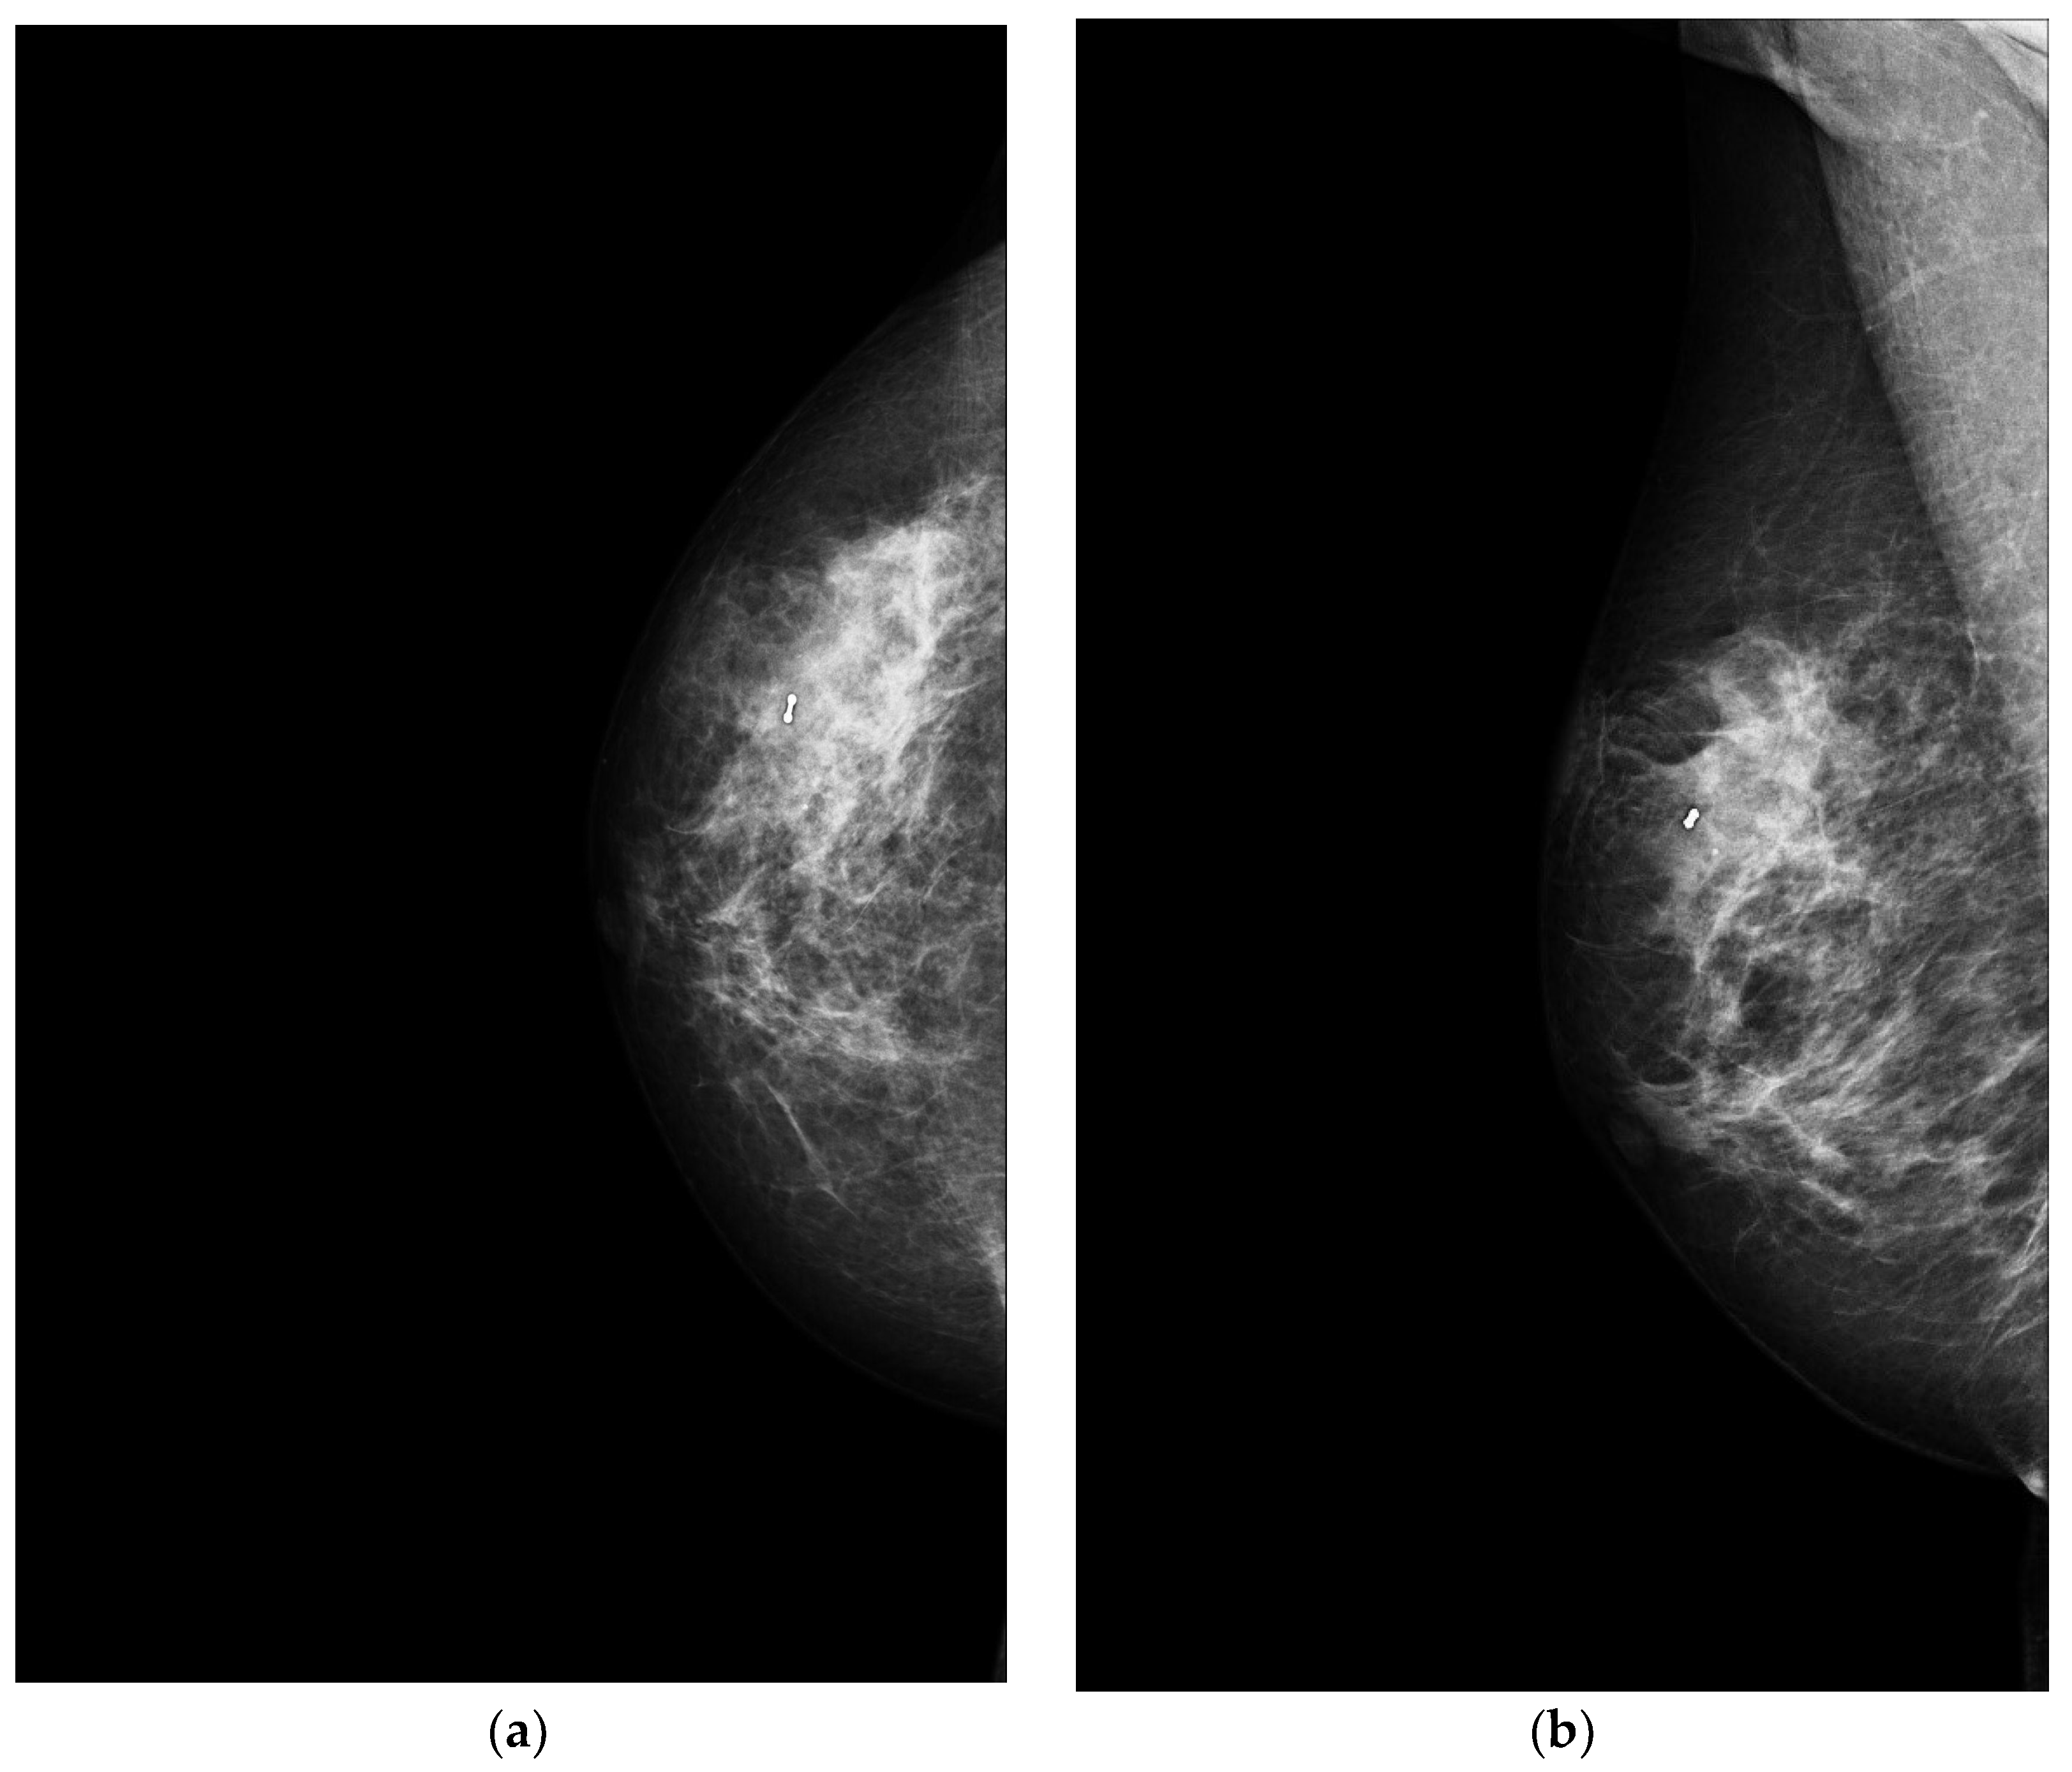

4.1. Mammography